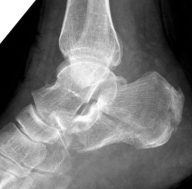

众所周知,跟骨是我们人体足弓的重要组成部分,它对我们站立负重及行走功能至关重要。因此,所谓跟骨骨折,顾名思义就是指正常的跟骨骨质结构的连续性或完整性遭到了破坏。它是创伤骨科中十分常见的一种损伤,约占全身骨折的2%,跗骨骨折的60%,常因高能量损伤引起(如高坠伤、汽车挤压伤等),受伤人群主要以青壮年居多。

伤后患者的临床表现主要包括:足跟部肿痛、皮下瘀斑、局部压叩痛、足弓变低平、足跟增宽、足底变长以及伤足不能下地负重等。

回到前文所述的患者程某,其X线片及CT检查提示其骨折系波及关节面的严重粉碎性骨折,具有明确的手术指征。